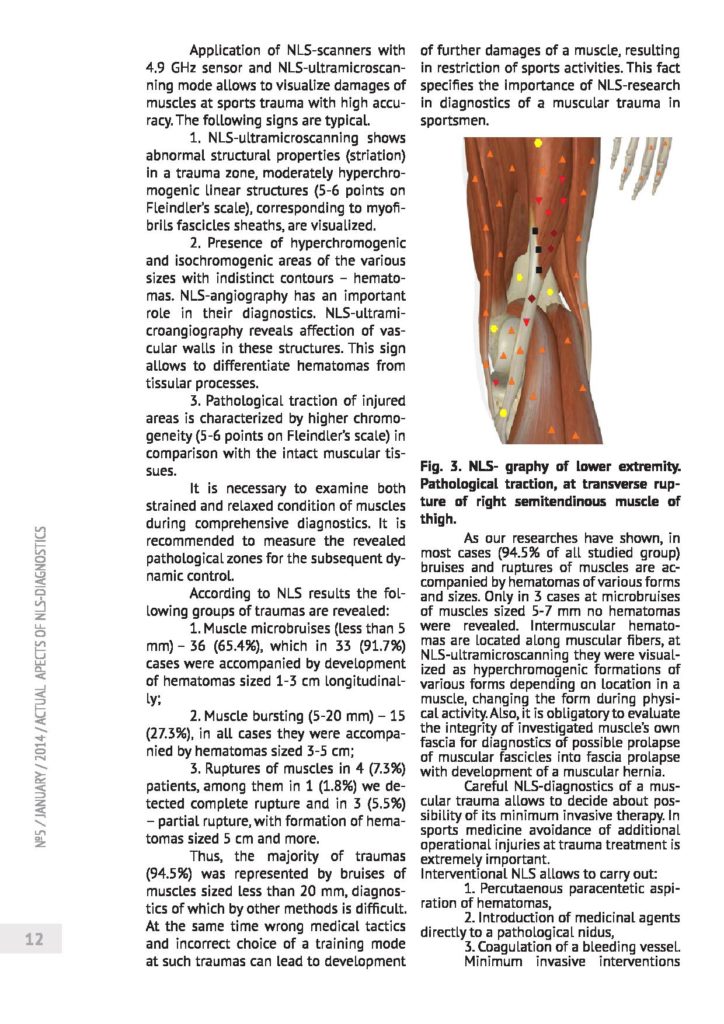

NLS - diagnostyka urazów mięśni u sportowców